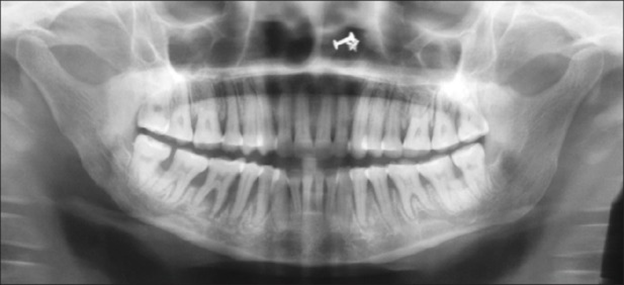

Radiographs may show varying degrees of bone resorption in patients with scleroderma. Mandibular resorption has been reported in 10% to 33% of patients with systemic sclerosis.11 Osteolysis is documented resorption of the mandibular angle and condyle of adult patients with scleroderma (see Figure 3). The etiology is not known. However, it is theorized that:

- Tightening of facial skin may exert excessive pressure on the mandible and induce bone loss

- Vasculopathy associated with systemic scleroderma may diminish the blood supply to the mandible and induce bone loss

- Atrophy of the muscles of mastication may lead to cone necrosis.

Uniform widening of the periodontal ligament space, especially around posterior teeth, is common.4,11

- Microstomia may increase difficulty in taking radiographs; use a size 0 or 1 sensor and regular panoramic radiographs to screen for bone resorption.3